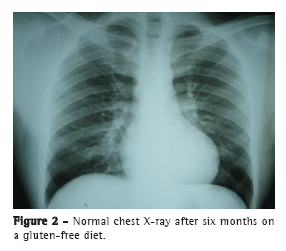

Com a instituição da dieta livre de glúten, houve regressão das lesões pulmonares e melhora clínica após seis meses. Até o momento da redação desta carta, o paciente encontrava-se em acompanhamento no serviço de pneumologia, assintomático, com radiografia de tórax e níveis de hemoglobina normais (Figura 2).